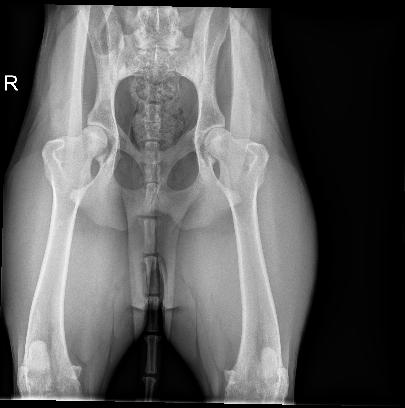

Ruby’s x-rays have been reviewed by a prominent ACVR member of my profession. We discussed the need to make sure she wasn’t an LTV (Lumbosacral Transitional Vertebrae)

dog, and it appears she is not. Her latest X-rays show the first, third and fifth coccygeal vertebrae are actually hemivertebrae creating a really uneven tailset area. An MRI might be in her future to help identify the reason for the pain and prolonged defecation, but not yet. She is a ‘high tail kink’ dog at this time. Kinked tails are supposed to be innocuous. But, that is not the case here. Her pain is real. My family and I will care for her and offer her a performance life as part of our pack. We lovingly call her “Aunt Ruby” already. She has had chiropractic work done and has had sporadic doses of anti-inflammatory medication if she is hurting.

Ruby in Stack Kink in tailset and her xrays